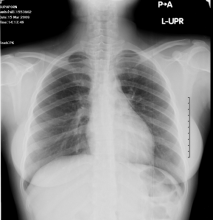

On examination she was look well. Her pulse rate was 92 beats/min, blood pressure was 100/67 mmHg, respiratory rate was 20 breaths/min, and oxygen saturation was  99 % on room air. Chest examination was normal, no subcutaneous emphysema and normal heart sound. A 12-lead electrocardiogram showed normal sinus rhythm. Chest X-ray demonstrated a pneumopericardium (Fig. 1) which was confirmed by computed tomography (Fig 2). The routing laboratory tests were also unremarkable. There was no evidence of other abnormalities. Gastrografin swallow show no leak or any other abnormality (Fig. 3)

Fig 1: Spontaneous pneumopericardium was show as a radiolucency band at Left heart boarder (arrows)